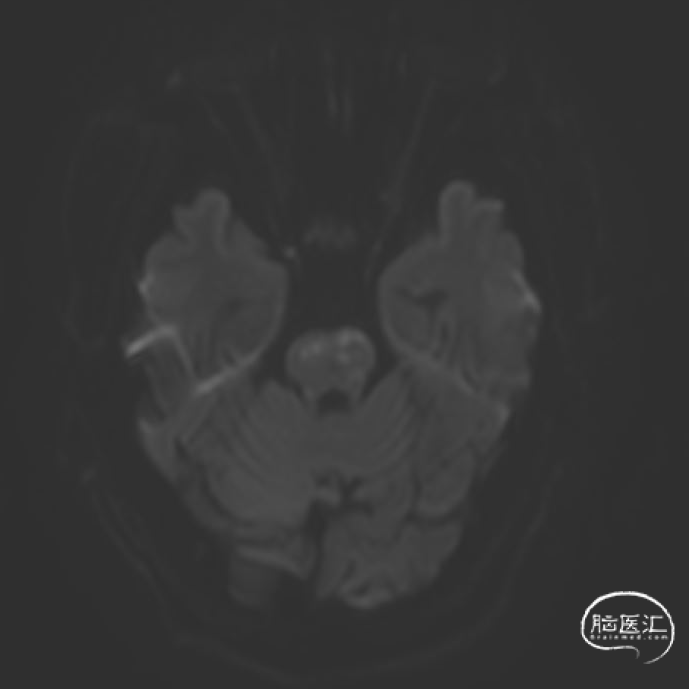

➢2023年11月06日

头颅MRI平扫:脑桥、左侧中脑、左侧桥臂急性脑梗死。

➢2023年11月14日

头颅MRI平扫+HRMRI:脑桥、中脑急性/亚急性脑梗死;双侧桥臂变性。

HRMRI:基底动脉闭塞并斑块合并局部出血;左侧大脑后动脉P1段斑块形成,相应管腔闭塞,左侧椎动脉V2-V4段斑块形成,相应管腔中重度狭窄,左侧椎动脉V4段管壁弥漫性增厚,相应管腔中度狭窄;右侧大脑后动脉纤细。